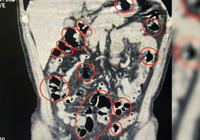

Mide ve bağırsaklarından uyuşturucu çıktı Bitlis'te üzerlerinde yapılan aramada ve mide ile bağırsaklarında toplam 50 kapsül halinde 385 gram metamfetamin ele geçirilen 2 şüpheli gözaltına alındı.